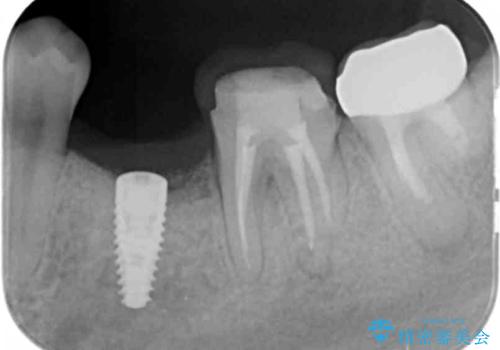

- 残していた乳歯がぐらつき始め、抜去ののちのインプラント治療を希望され来院されました。

乳歯を抜去して歯ぐきの状態が落ち着いたのち、骨の増成を伴うインプラント治療を行い機能の回復を図ります。

生まれつき永久歯の欠損がある場合、乳歯が大人になっても残っている場合があります。

残念ながらぐらつきが大きくなり、残すことが難しくなり抜去したのちインプラントを用いて咬合機能の回復をしっかりと行いました。